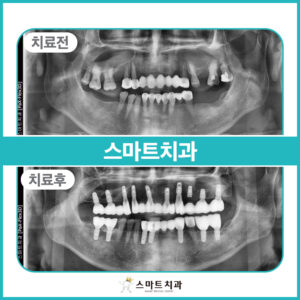

안락동임플란트치과추천 편안한 식사를 위해

안녕하세요. 안락동임플란트치과추천 스마트치과입니다. 우리의 신체 기관 중 치아는 저절로 재생이 되지 않기 때문에 평생 동안의 관리가 필요합니다. 건강한 치아를 가지고 있는 것이 오복이라고 불릴 정도로 살아가는 데 있어 중요한 부분이기 때문입니다. 100세 시대라고 불리는 현대사회에서 기대수명이 늘어나면서 치아의 수명도 길어져야 하는 것이 맞지만 제대로 관리가 이루어지지 않거나, 사고나 노화 다양한 더보기…